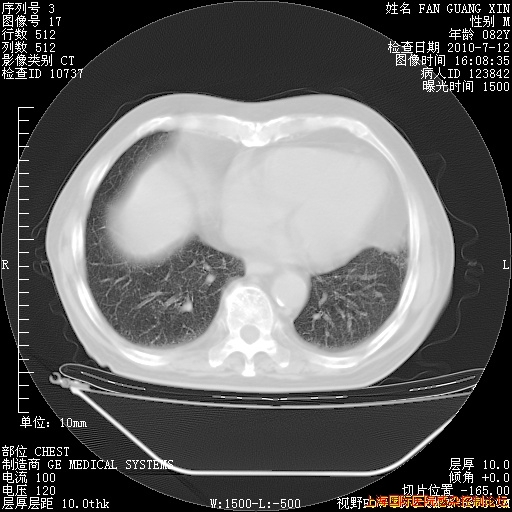

今天复查CT

今天CT

整整相隔30天的肺部CT好像有所好转啊。甲强龙减量第3天,需要观察体温。